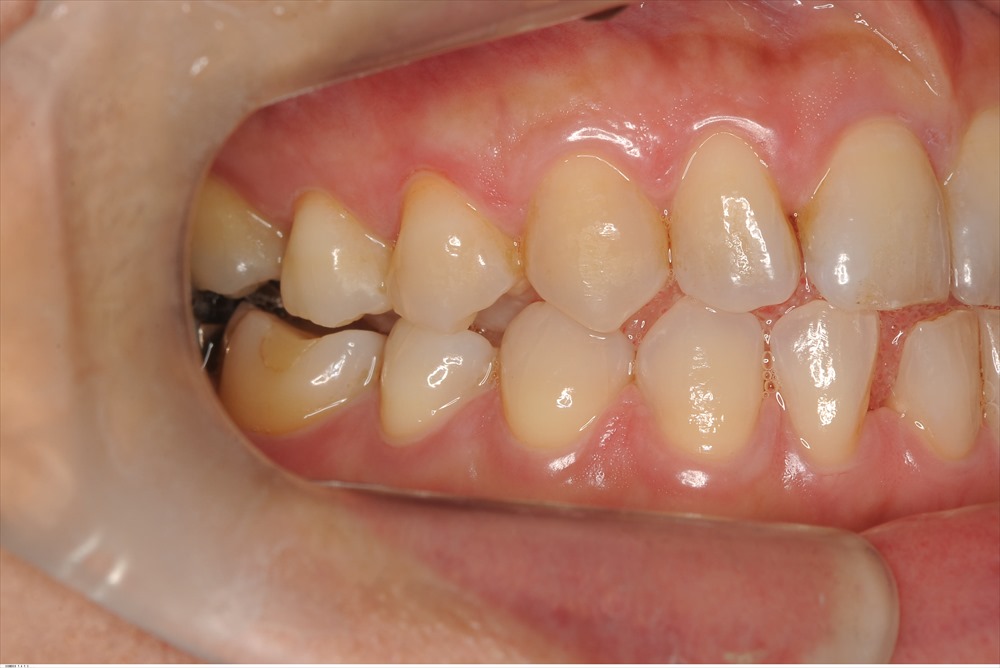

右下の一番奥の歯の後ろ側に10mmのポケットがありました。

この様な骨内欠損です。